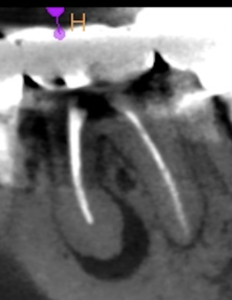

#19 Re-RCT 1yr recall(2026.1.13)

#19

MB

ML

D

術前に大きな根尖病変が存在していたM根のそれは消失はしていないが大幅に縮小し、

術前に根尖病変がなく再根管形成・充填しなかったD根はやはり依然として根尖病変はできていない。

このケースでも

Selective Root Canal Retreatmentが奏功している。

ということで根尖病変は完全消失はしていないのでまた1年後に経過を見せてもらうことになった。